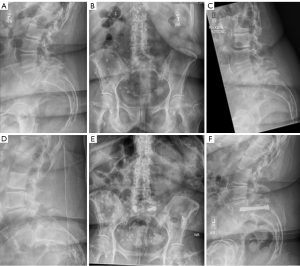

Step-by-step description

Mean preoperative upright anterior translation was 18 (range, 15.6–20.5) mm. Four patients were qualified as Meyerding grade two spondylolisthesis and one patient was a Meyerding grade three. Mean difference in L5–S1 anterolisthesis between flexion and extension was 4.4 (range, 3.5–5) mm.

Complications and revisions

Mean operative time was 164 (range, 124–233) min. No patients in this series had any reported complications or returned to the operating room. All five patients had a minimum of 6-month post-operative radiographs. No implant complications were noted. All patients achieved solid radiographic fusion at the last follow-up.